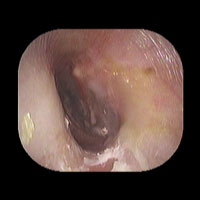

右急性中耳炎(重症) 鼓膜切開

鼓膜が赤く腫れて、鼓膜の奥に白い膿がたまっています。高熱が続き、痛みがとても強かっため、鼓膜切開を行いました。

9日目にほぼ治りました。当院ではできる限り鼓膜切開を行わずに治すことを考えていますが、必要な時はお勧めしています。

初診時 鼓膜切開の直後